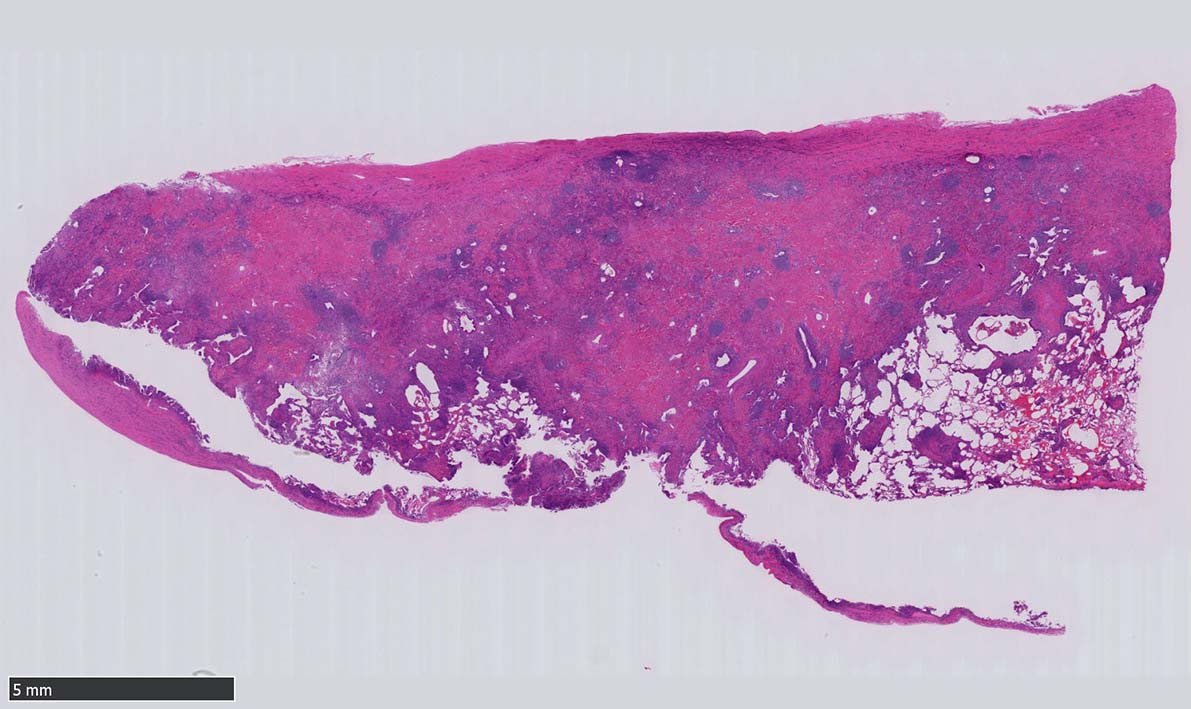

12 x 3.8mm, 腫大した鼠径リンパ節が生検された.--クリックで大きな画像がみられます.|

萎縮した胚中心をマントル細胞が取り囲む濾胞構造がびまん性に認められる. 濾胞間には,形質細胞が密に認められる.

IL-6高値. 検査値からは Castleman disease がIgG4関連リンパ節症よりも適切と考えられる. 次第に, 胸部X-pの増悪あり. rt.lung B4a, B6bからVATSが施行された.

肺VATS組織